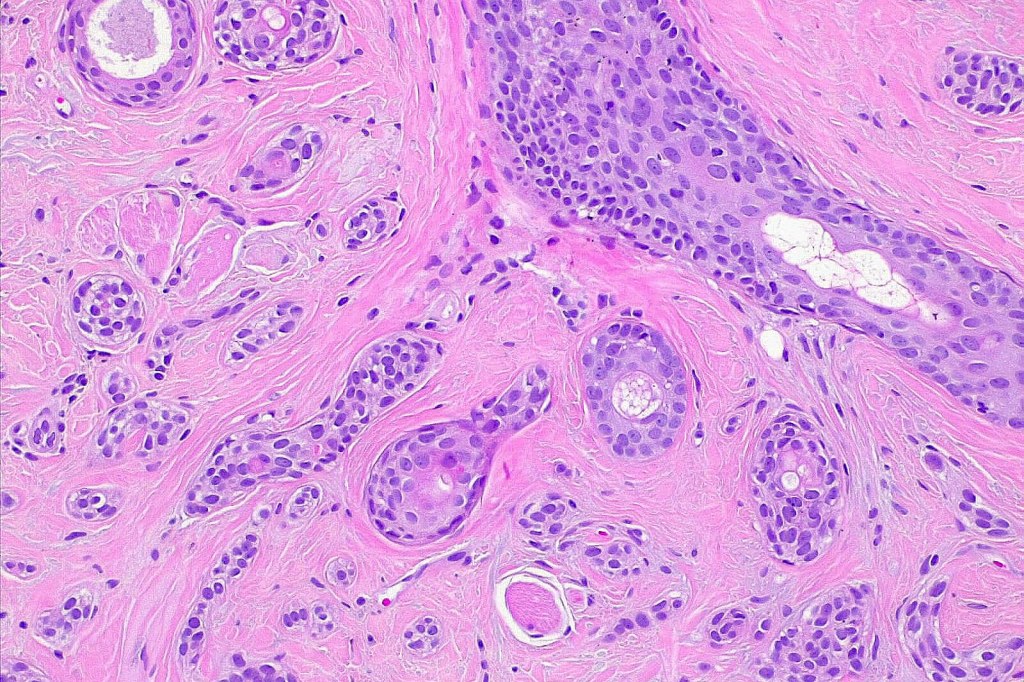

Histological features

•Dermal lesion composed of epithelial stands & ducts dispersed in a fibrous stroma

•Tadpole configuration- ducts with epithelial strands

Intracytoplasmic lumina

•Absence of pleomorphism or mitotic activity